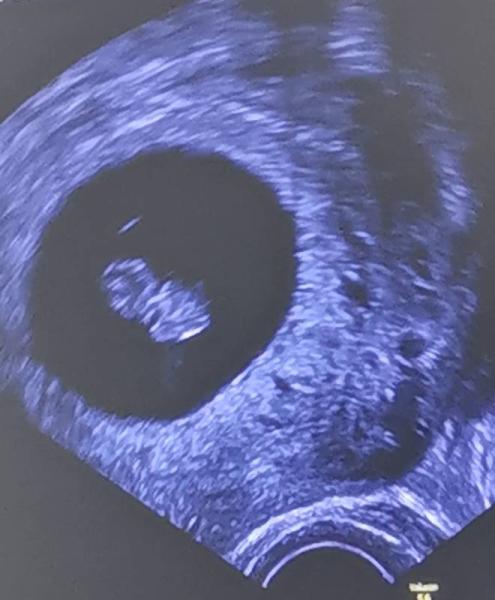

Oh gott ich schwebe vor Liebe, 1cm und 7mm gross blutwerte auch top! Alles super oh maaannn

Ohhh Leute da ist meine grosse Liebe wo ihr da seht

Das freut mich GlĂŒckwunsch ... Ein sĂŒĂŸes GummibĂ€rchen

Zauberhaft Und es sieht aus als ob dein kleines GummibĂ€rchen auch schwebt Naja, tut es ja auch. Herzlichen GlĂŒckwunsch!

so ein sĂŒĂŸes foto! der/die kleine schwebt auch :)